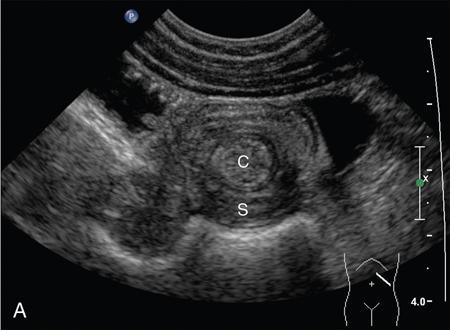

Ajay Taranath, Lino Piotto Intussusception is a common cause of acute abdominal pain in children. In this condition, a portion of the bowel wall, the intussusceptum, invaginates into the lumen of the portion of the bowel immediately distal to it, the intussuscipiens. It occurs most commonly in the first two years of life but is sometimes seen in older children. Once the invagination process has begun, the first part of the intussusceptum (the head) is pushed distally by peristalsis dragging the wall of the bowel with it. This tends to be progressive once it starts and as the invagination continues, interference with the blood supply of the intussusceptum causes venous occlusion and subsequent mucosal congestion. In advanced cases, the vascular compromise may result in the passage of blood-stained mucus through the rectum (red-currant jelly). Intussusception may be idiopathic or may be due to a pathologic ‘lead point’ such as a Meckel’s diverticulum, duplication cyst or neoplastic mass within the bowel wall. Most patients under the age of 2 years are in the idiopathic group. These are thought to be associated with thickening of bowel wall caused by hyperplasia of Peyer’s patches in response to a recent viral infection. Pathologic lead points are much more common in patients older than 4 years. For this reason, the head of the intussusceptum in these patients should be scanned carefully for evidence of a lead point. Intussusception is usually described according to the bowel that is involved. Those involving only small bowel include jejuno-jejunal (jejunum into jejunum) and ileo-ileal (ileum into ileum), are often seen as an incidental finding in abdominal sonography and only infrequently require intervention, when they have caused a bowel obstruction (Fig. 7.12.1A and B). Those involving large bowel include ileo-colic (ileum into colon), ileo-ileo-colic (ileum into ileum and then into colon) and colo-colic (colon into colon) and almost always require intervention. The most common of these is the ileo-colic type, in which the terminal ileum invaginates the colon through the ileo-caecal valve. The longer the intussusception persists, the greater the likelihood of gut necrosis and the need for surgical resection. Typically, children with intussusception will present with some or all of the following clinical features: attacks of colic, vomiting, blood and mucus per rectum, palpable abdominal mass. The attacks of colic are often associated with drawing-up of the legs. The duration of symptoms is usually less than 48 hours. The peak incidence is around 18 months though it can occur in children as young as 5 months and as old as 15 years. Traditionally, children suspected of suffering from an ileo-colic intussusception would be investigated with supine, erect and occasionally prone plain radiographs. When the clinical suspicion was high, the only way to confirm or exclude the presence of an intussusception was to perform a barium enema. A hydrostatic reduction using barium would then be employed to reduce an ileo-colic intussusception if one was found. More recently, pneumatic reductions have become the method of choice in many departments; benefits of this method include excellent reduction results and less radiation exposure than a barium enema. Pneumatic reductions have also shown to have greater reduction success rates than with barium. However, depiction rates of a pathological lead point on air enema are poor. Navarro et al. demonstrated a depiction rate of 11% in their study. Miller et al. showed a slightly higher depiction rate of 16%. Also, it must be noted that a successful reduction by an air enema cannot exclude a pathological lead point. In particular, lesions within the small bowel can be overlooked. Reduction rates also diminish when a pathological lead point is involved. Navarro et al. achieved a reduction rate of 29% in children presenting with their first episode of intussusception resulting from a pathological lead point. The relatively high-radiation dose from enema reductions was a significant factor in the development of ultrasound techniques, initially used only to identify those patients who had intussusception and therefore required a reduction. As a natural progression, the use of ultrasound in some institutions has been extended to monitoring of the reduction procedure. It is very important that the patient is well hydrated. It would be beneficial to have an intravenous access in all the patients with ileo-colic intussusception needing a pneumatic reduction. Administration of antibiotics may need consideration to ward off complications that might arise if there was an inadvertent perforation. It would be helpful to administer analgesics in consultation with the surgical team to help obtain compliance. The paediatric surgeon is in attendance. An 18 g cannula is kept handy to release the free air if a perforation occurs during the attempted reduction. The setup for a pneumatic reduction of intussusception (Fig. 7.12.2) consists of the following: (i) A cylinder of sterile medical air. (ii) A tube that leads away from the cylinder to a pressure limiting chamber. It has a dial indicating the pressure and a valve at the top of the chamber that will open if the pressure attained intraluminally goes over what has been set. (iii) A tube leading from the pressure-limiting chamber to a Foley’s catheter that is placed in the rectum. (iv) A three-way Y-valve (that can be controlled by the operator’s thumb in case the pressure control needs to be achieved quickly) is interposed midway in the tube leading out of the pressure chamber. It is important to get a good seal at the rectum. The chamber pressure is set at 80 mm Hg at the start of the reduction. A thumb rule of 3 is followed in that if there is no success with reduction after employing a pressure of 80 mm Hg for 3 minutes, it is increased to 100 mm Hg for 3 minutes and if the operator is comfortable, to 110–120 mm Hg for 3 minutes. If reduction is not achieved, surgical intervention may need to be considered in consultation with the paediatric surgeons. The air insufflation is begun. Retrograde movement of the intussusceptum is tracked fluoroscopically. There may be a point when the intussusceptum reaches the ileo-caecal junction and fails to respond to the air insufflation. It would helpful for the patient as the ileo-colic intussusceptions without pathological lead points tend to reduce, albeit in a delayed manner. The procedure is concluded when the insufflated air enters the small bowel loops (Fig. 7.12.3A and B).